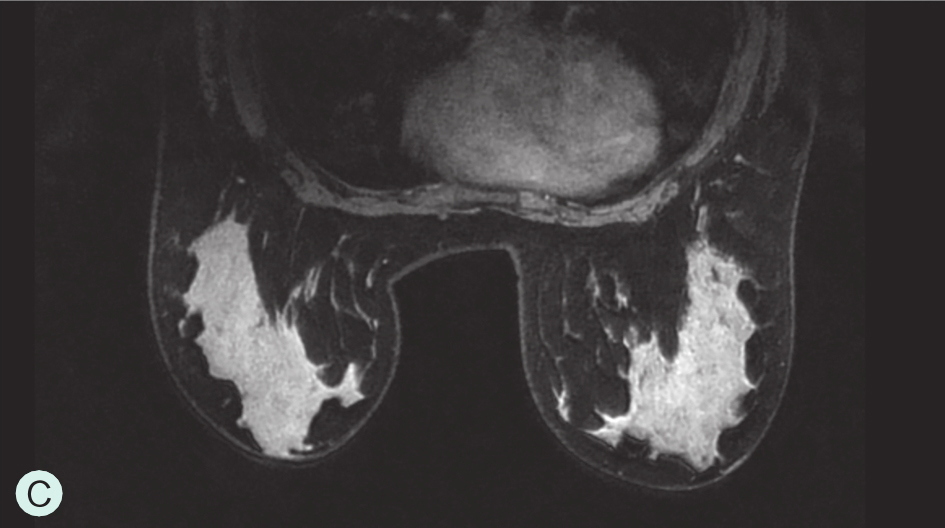

C级:不均匀致密型(可能掩盖小肿块)(图1-3-1C、图1-3-2C、图1-3-3C)。

图1-3-3 乳腺MRI不同乳腺密度

A.脂肪型;B.散在致密型;C.不均匀致密型;D.极度致密型